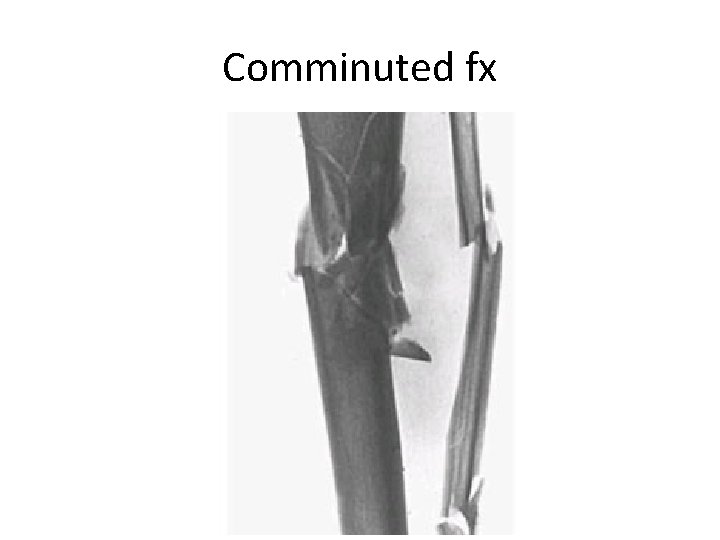

Fractures • Simple ; spiral, oblique and transverse • Complex – Complete separation of bone; major blow, intraarticular , comminution and segmental • Open vs close

Comminuted fx